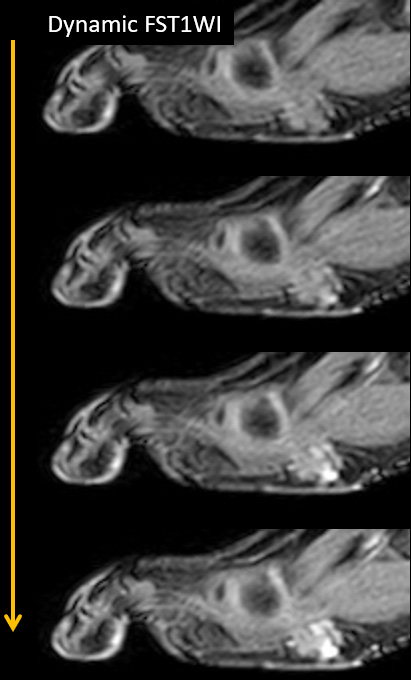

8歳男児 歩行時痛、足底部腫瘤

Dynamic FST1WI

- 【参考症例】